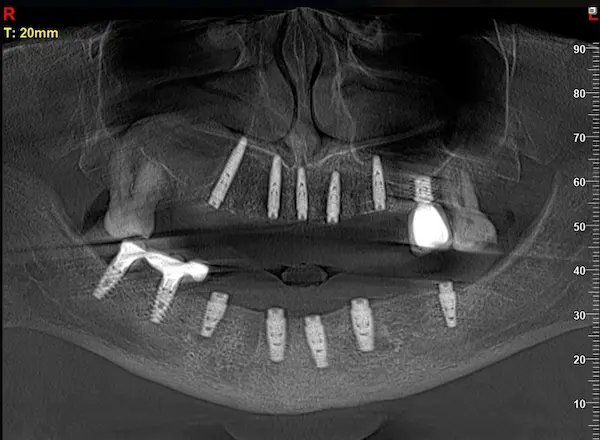

Сканы КТ имплантации зубов, 2026-04-18

Скан КТ, 2026-04-18

Сканы КТ имплантации зубов, 2026-04-18

Скан КТ имплантации зубов, 2026-04-17

Сканы КТ имплантации зубов, 2026-04-18

KT: имплантация зубов DentalKnysh, 2025-01-03, сканы

KT: имплантация зубов DentalKnysh, 2025-01-03, сканы

KT: имплантация зубов DentalKnysh, 2025-01-03, сканы

КТ имплантации зубов в DentalKnysh (10 имплантов), 2023-11-03

С 2023-09-05 по 2023-09-09 сканы КТ от 6 до 12 имплантов в DentalKnysh (4 фото):

Синуслифтинг и имплантация зубов, 6 имплантов, all-on-6, КТ скан 1, 2023-08-31

Фото отчет Имплантация зубов, 6 имплантов, КТ скан 3, 2023-08-31

Фото отчет Имплантация зубов, 8 имплантов, all-on-4, КТ скан 1, 2023-08-31